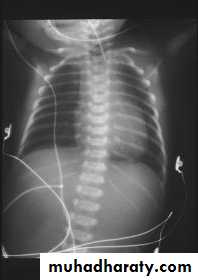

Diagnosis:-- CXRo Air & fluid filled loops of bowel in the chest.o Paucity of intestinal gas in the abdomen.o Mediastinal shift (heart shifted to the right).o Tip of NG tube seen in the chest.